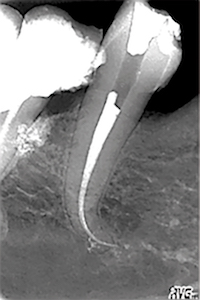

TP 11 - Endodontie : Préparation canalaire – système Race (FKG) - et obturation simplifiée

par Bertrand Khayat

Acquérir un geste rapide, précis et léger avec le système Race (FKG)

Discipline abordée : Endodontie.

La combinaison des instruments FKG Scout Race et de la séquence iRace offre une solution globale en rotation continue plus rapide et plus sûre dans la préparation canalaire » explique Bertrand Khayat, responsable de ce TP.

Et d’ajouter : « l’introduction d’un nouvel instrument rotatif à mémoire de forme permet un meilleur nettoyage sans élargissement du canal afin de préserver la résistance de la dent. »

Destiné aux omnipraticiens, ce TP vise à se familiariser avec le système Race, impliquant une technique récente et encore peu répandue mais qui présente de nombreux avantages. En effet, cet instrument permet de s’affranchir complètement de l’instrumentation manuelle, en particulier dans la phase initiale du traitement. Le cathétérisme est alors réalisé de manière mécanisée avec des instruments rotatifs très particuliers qu’il faut savoir maîtriser.

Concrètement, dans un premier temps, une phase théorique concise et pratique présentera le système Race avant une démonstration sur un bloc en plastique. Encadrés par l’équipe pédagogique, les participants réaliseront ensuite des préparations canalaires avec le système Race sur des blocs en plastique et des dents naturelles extraites qu’ils auront spécifiquement apportées pour le TP.

L’après-midi, ils obtureront les dents préalablement préparées. Deux techniques d’obturation seront proposées : la technique de condensation thermomécanique et la technique mono-cône biocéramique.

L’objectif : maîtriser ces deux techniques afin d’élargir le panel de choix du praticien.

L’accent sera mis tout au long de la séance sur la dynamique instrumentale spécifique de l’instrument Race qui nécessite un geste rapide, précis et léger.

Responsable scientifique : Bertrand Khayat.

Equipe pédagogique : Cauris Couvrechel, Julien Dusart, Guillaume Jouany.

Les objectifs de la formation :

- Se familiariser avec le système Race.

- Comprendre la dynamique spécifique de l’instrument.

- Mettre les deux techniques d’obturations proposées en rapport avec cette technique de préparation